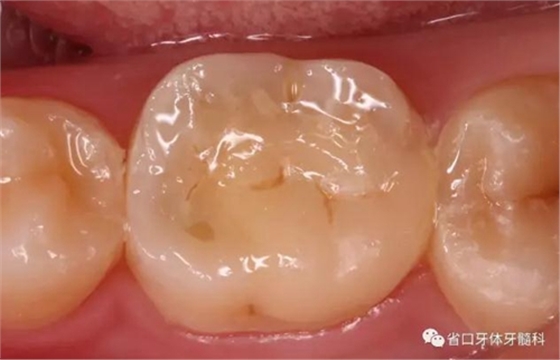

圖8 嵌體修復后3個月復查

圖9 根管治療術后20個月(嵌體修復后3個月)復查